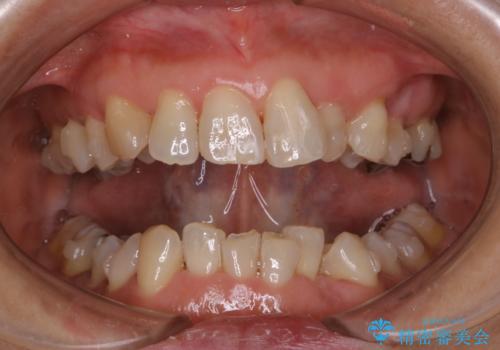

インビザラインの治療中の患者様のクリーニング前後写真です。

- インビザラインの矯正治療中に歯石や着色(ステイン)が付着してしまっていたため、歯科衛生士による専門的クリーニングを行いました。

今回はお口全体に歯石や着色(ステイン)が付着していたため、自費のPMTC(クリーニング)60分コースをご案内し、徹底的に除去しました。